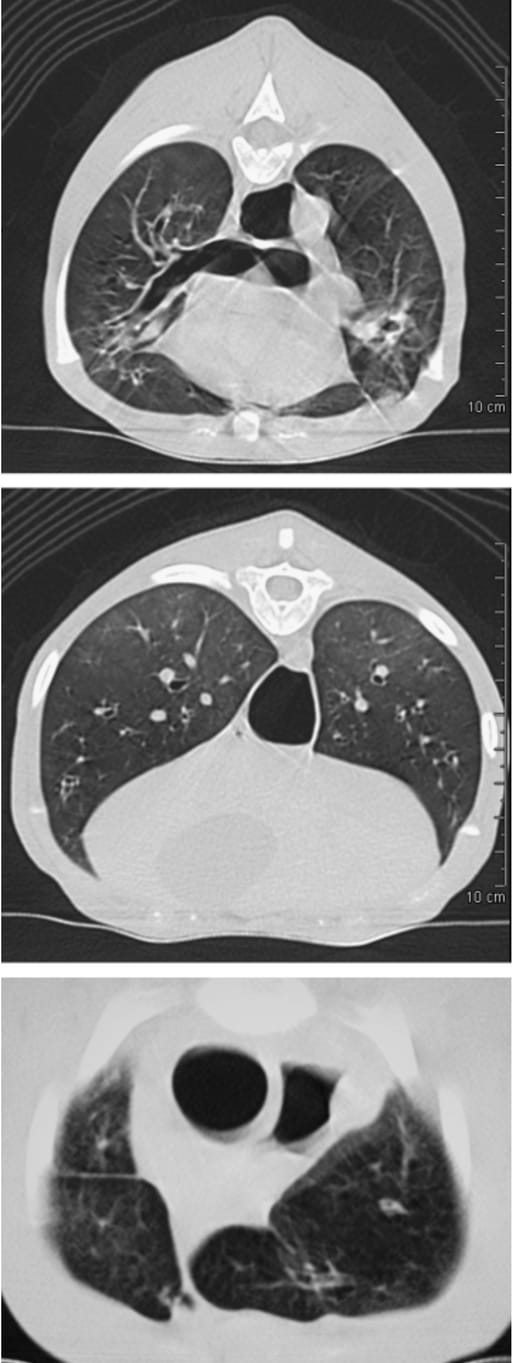

Radiographs showed hyperinflation and mild bronchointerstitial patterns that did not reflect the clinical severity. CT revealed diffuse bronchial wall thickening, bronchiectasis, abnormal visibility of peripheral bronchioles, patchy interstitial opacities, and lung consolidation, particularly in ventral regions. PFT demonstrated reduced diffusing capacity, mild reduction in lung compliance, and significant expiratory flow limitation due to small airway obstruction. Histopathology confirmed pan-acinar emphysema, chronic active bronchiolitis, and mucous obstruction of airways. The small airway disease was deemed the primary pathology, leading to dynamic air trapping and hyperinflation.

Fig. 2. (A, B) Transverse thoracic HRCT images at T5 and the T10–11 disk space, respectively. (A) Bronchial wall thickening, bronchiectasis and the abnormal visualization of bronchi or bronchioles into the periphery of the lung. (B) Diffuse bronchial wall thickening and the patchy diffuse homo- geneous opacity present in the dorsal aspect of the lungs. (C) Transverse thoracic spiral CT image at the C7–T1 disk space. Note the rounded ap- pearance of the cranial lung lobe margins. HRCT, high-resolution computed tomography; CT, computed tomography.